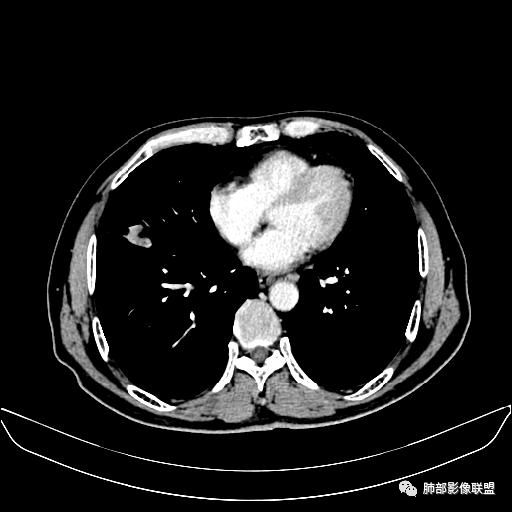

入院CT

老年男性,因“咳嗽咳痰1月余。”入院。病程中咳嗽咳痰,咳黄白痰,间断咯少许鲜红色痰血。PPD阳性。胸CT:右肺中叶外侧段支气管管腔阻塞,大片实性病变,病灶边缘光滑,部分边缘膨隆,可见分叶,肺门及纵隔可见肿大淋巴结,并可见钙化。增强可见病灶明显强化,而且延迟强化明显,病灶内多发低密度区,内见血管影,血管变细、部分血管破坏。考虑恶性病变可能性大,鉴别慢性肉芽肿性病变。

右肺中叶外侧段管腔阻塞、实性病变,病灶边缘光滑,可见分叶,肺门及纵隔可见肿大淋巴结,并可见钙化。增强可见病灶内多发低密度区。

老年男性,咳嗽、咳痰1月余,间断血痰。PPD阳性。

胸CT:跨叶大肿块,主体在中叶,右中叶外侧段支气管阻塞,病灶部分边缘膨隆,可见分叶,部分边缘平直,肺门及纵隔可见肿大淋巴结。增强病灶不均匀强化,延迟强化明显,病灶内多发低密度区,内见血管飘浮,部分血管变细、模糊。考虑:恶性病变可能性大,大细胞?淋巴瘤?鉴别慢性肉芽肿性病变。